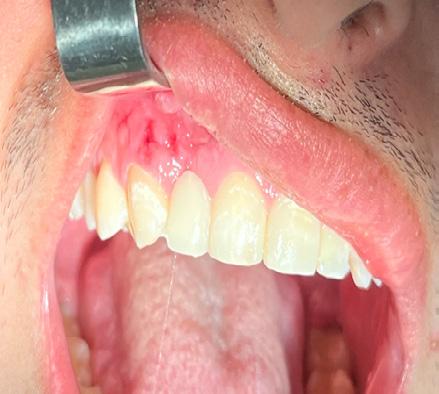

Issuu converts static files into: digital portfolios, online yearbooks, online catalogs, digital photo albums and more. Sign up and create your flipbook.